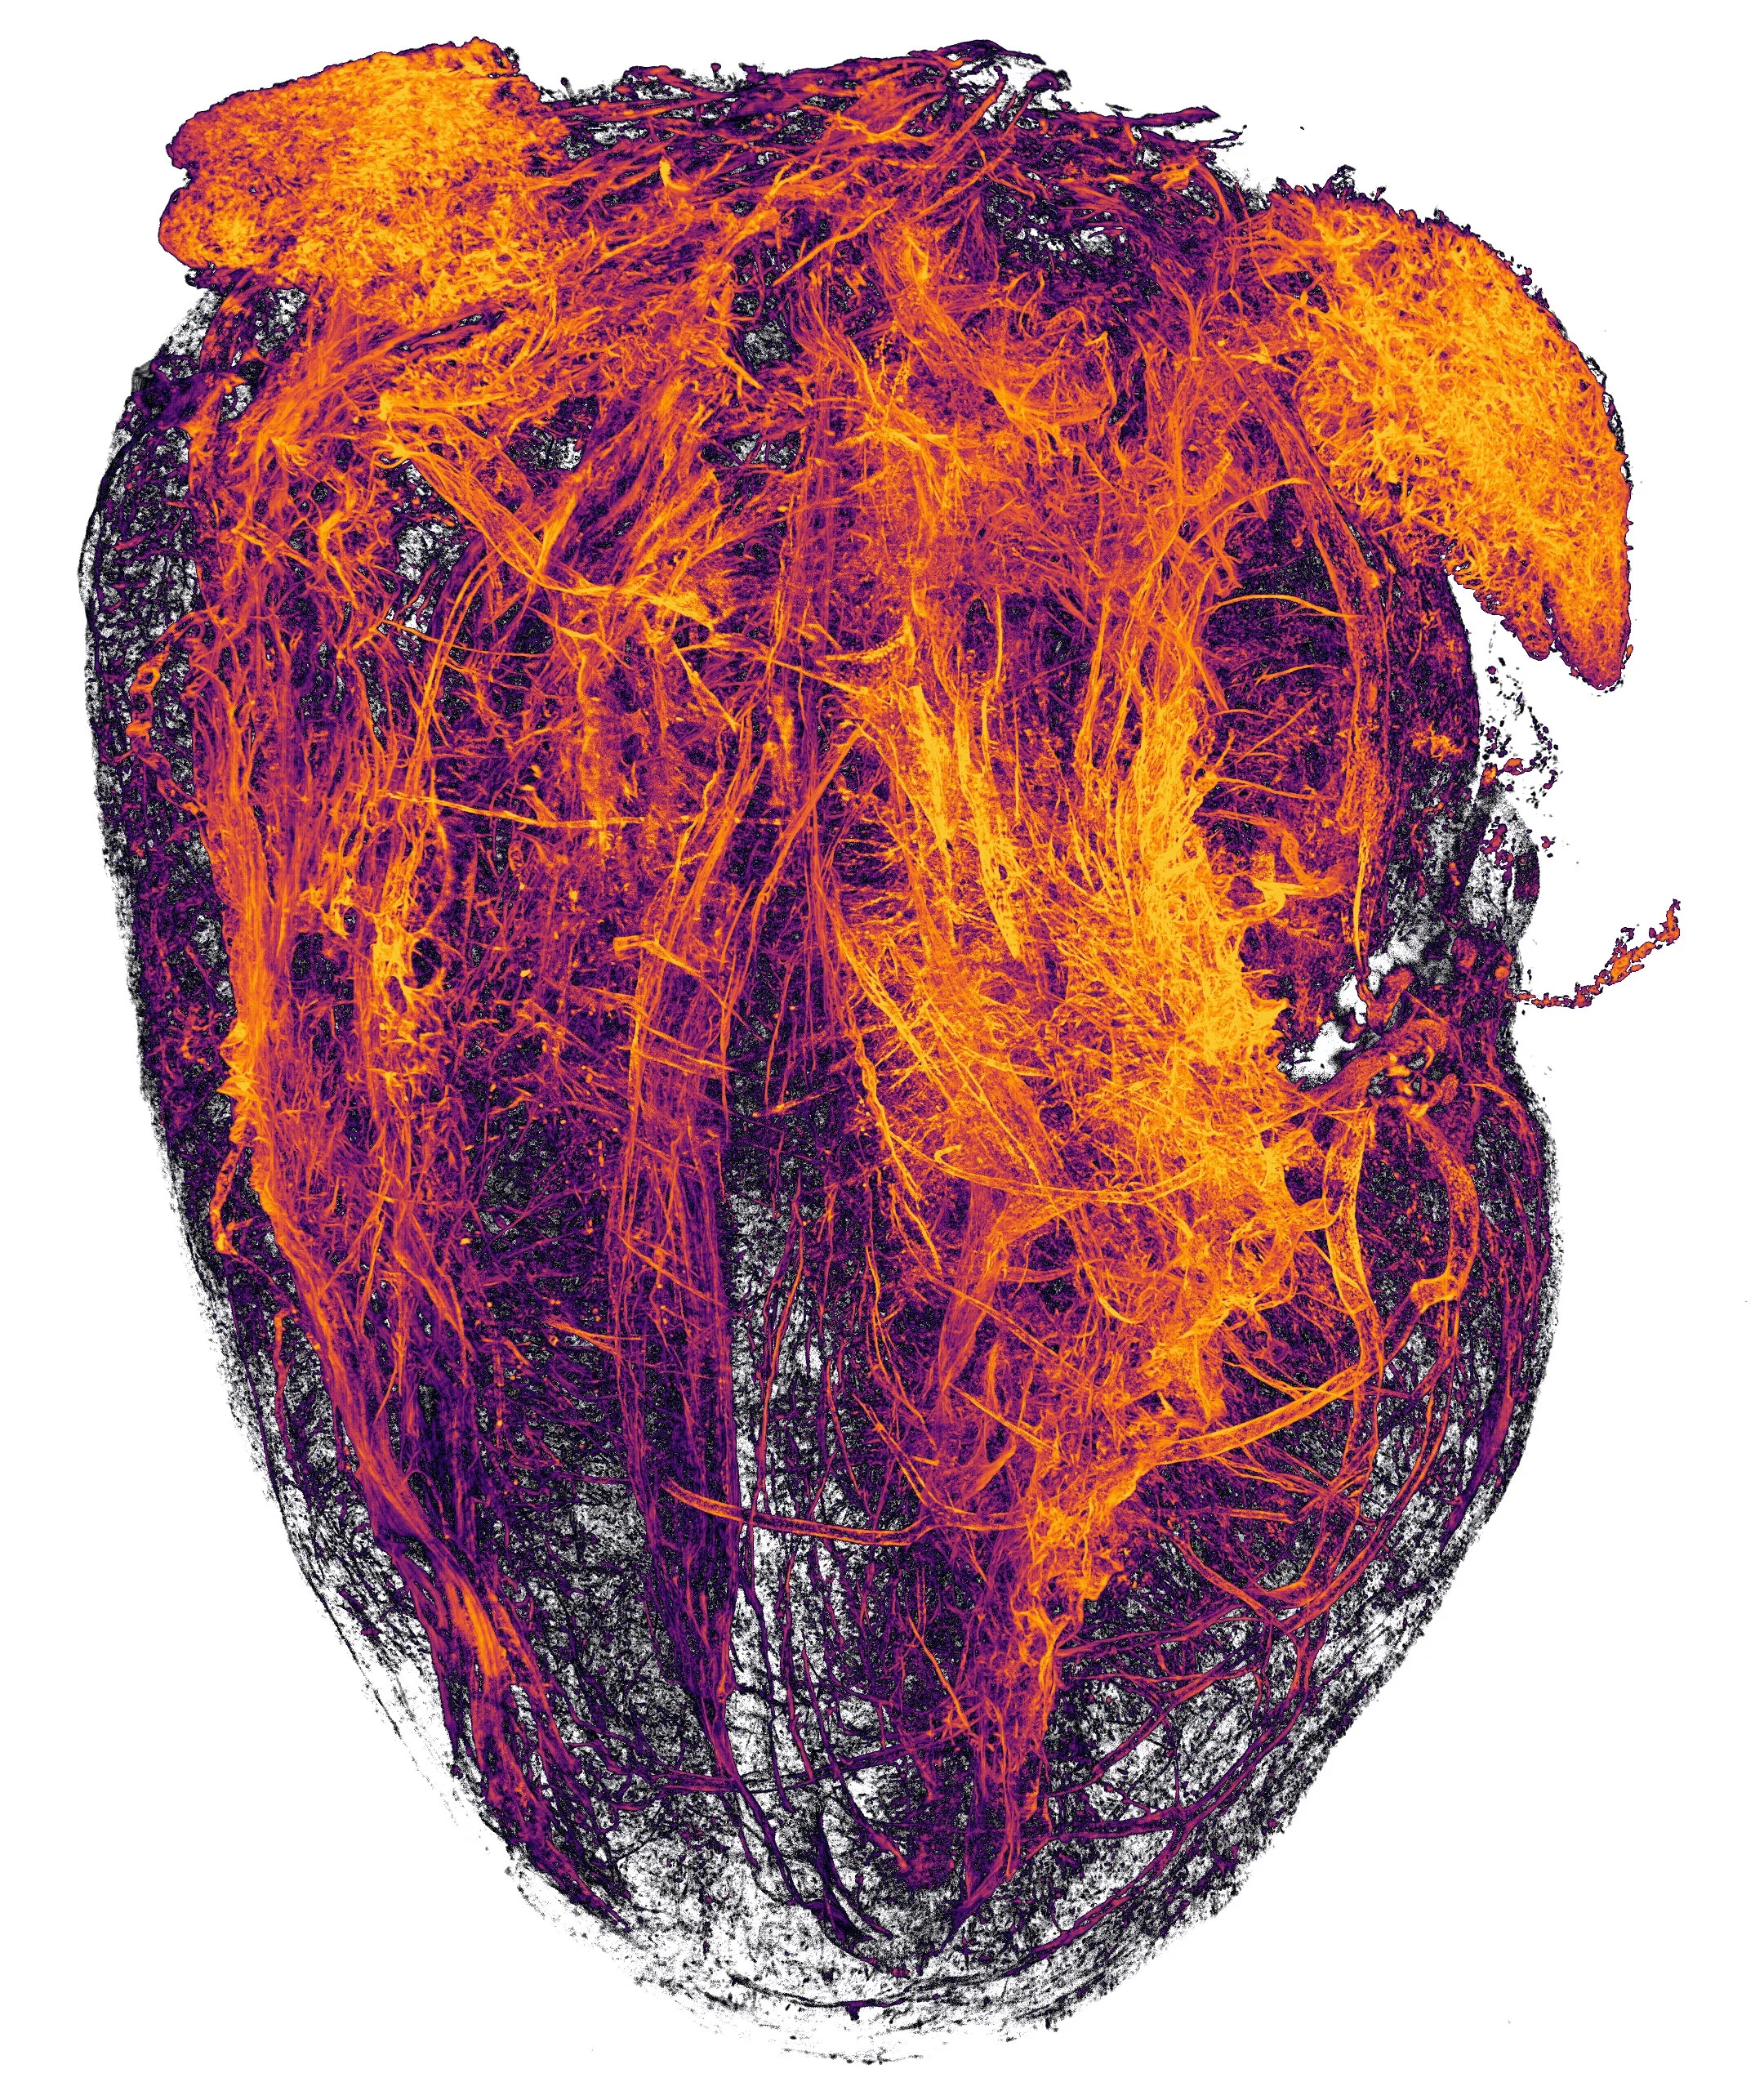

Первое место занял снимок эмбриона черепашки, авторства Терезы Каглер и Терезы Згобы. Всего отобраны 20 финалистов, фотографии которых мы публикуем ниже. Победителей предыдущих годов можно посмотреть в галерее на официальном сайте конкурса.